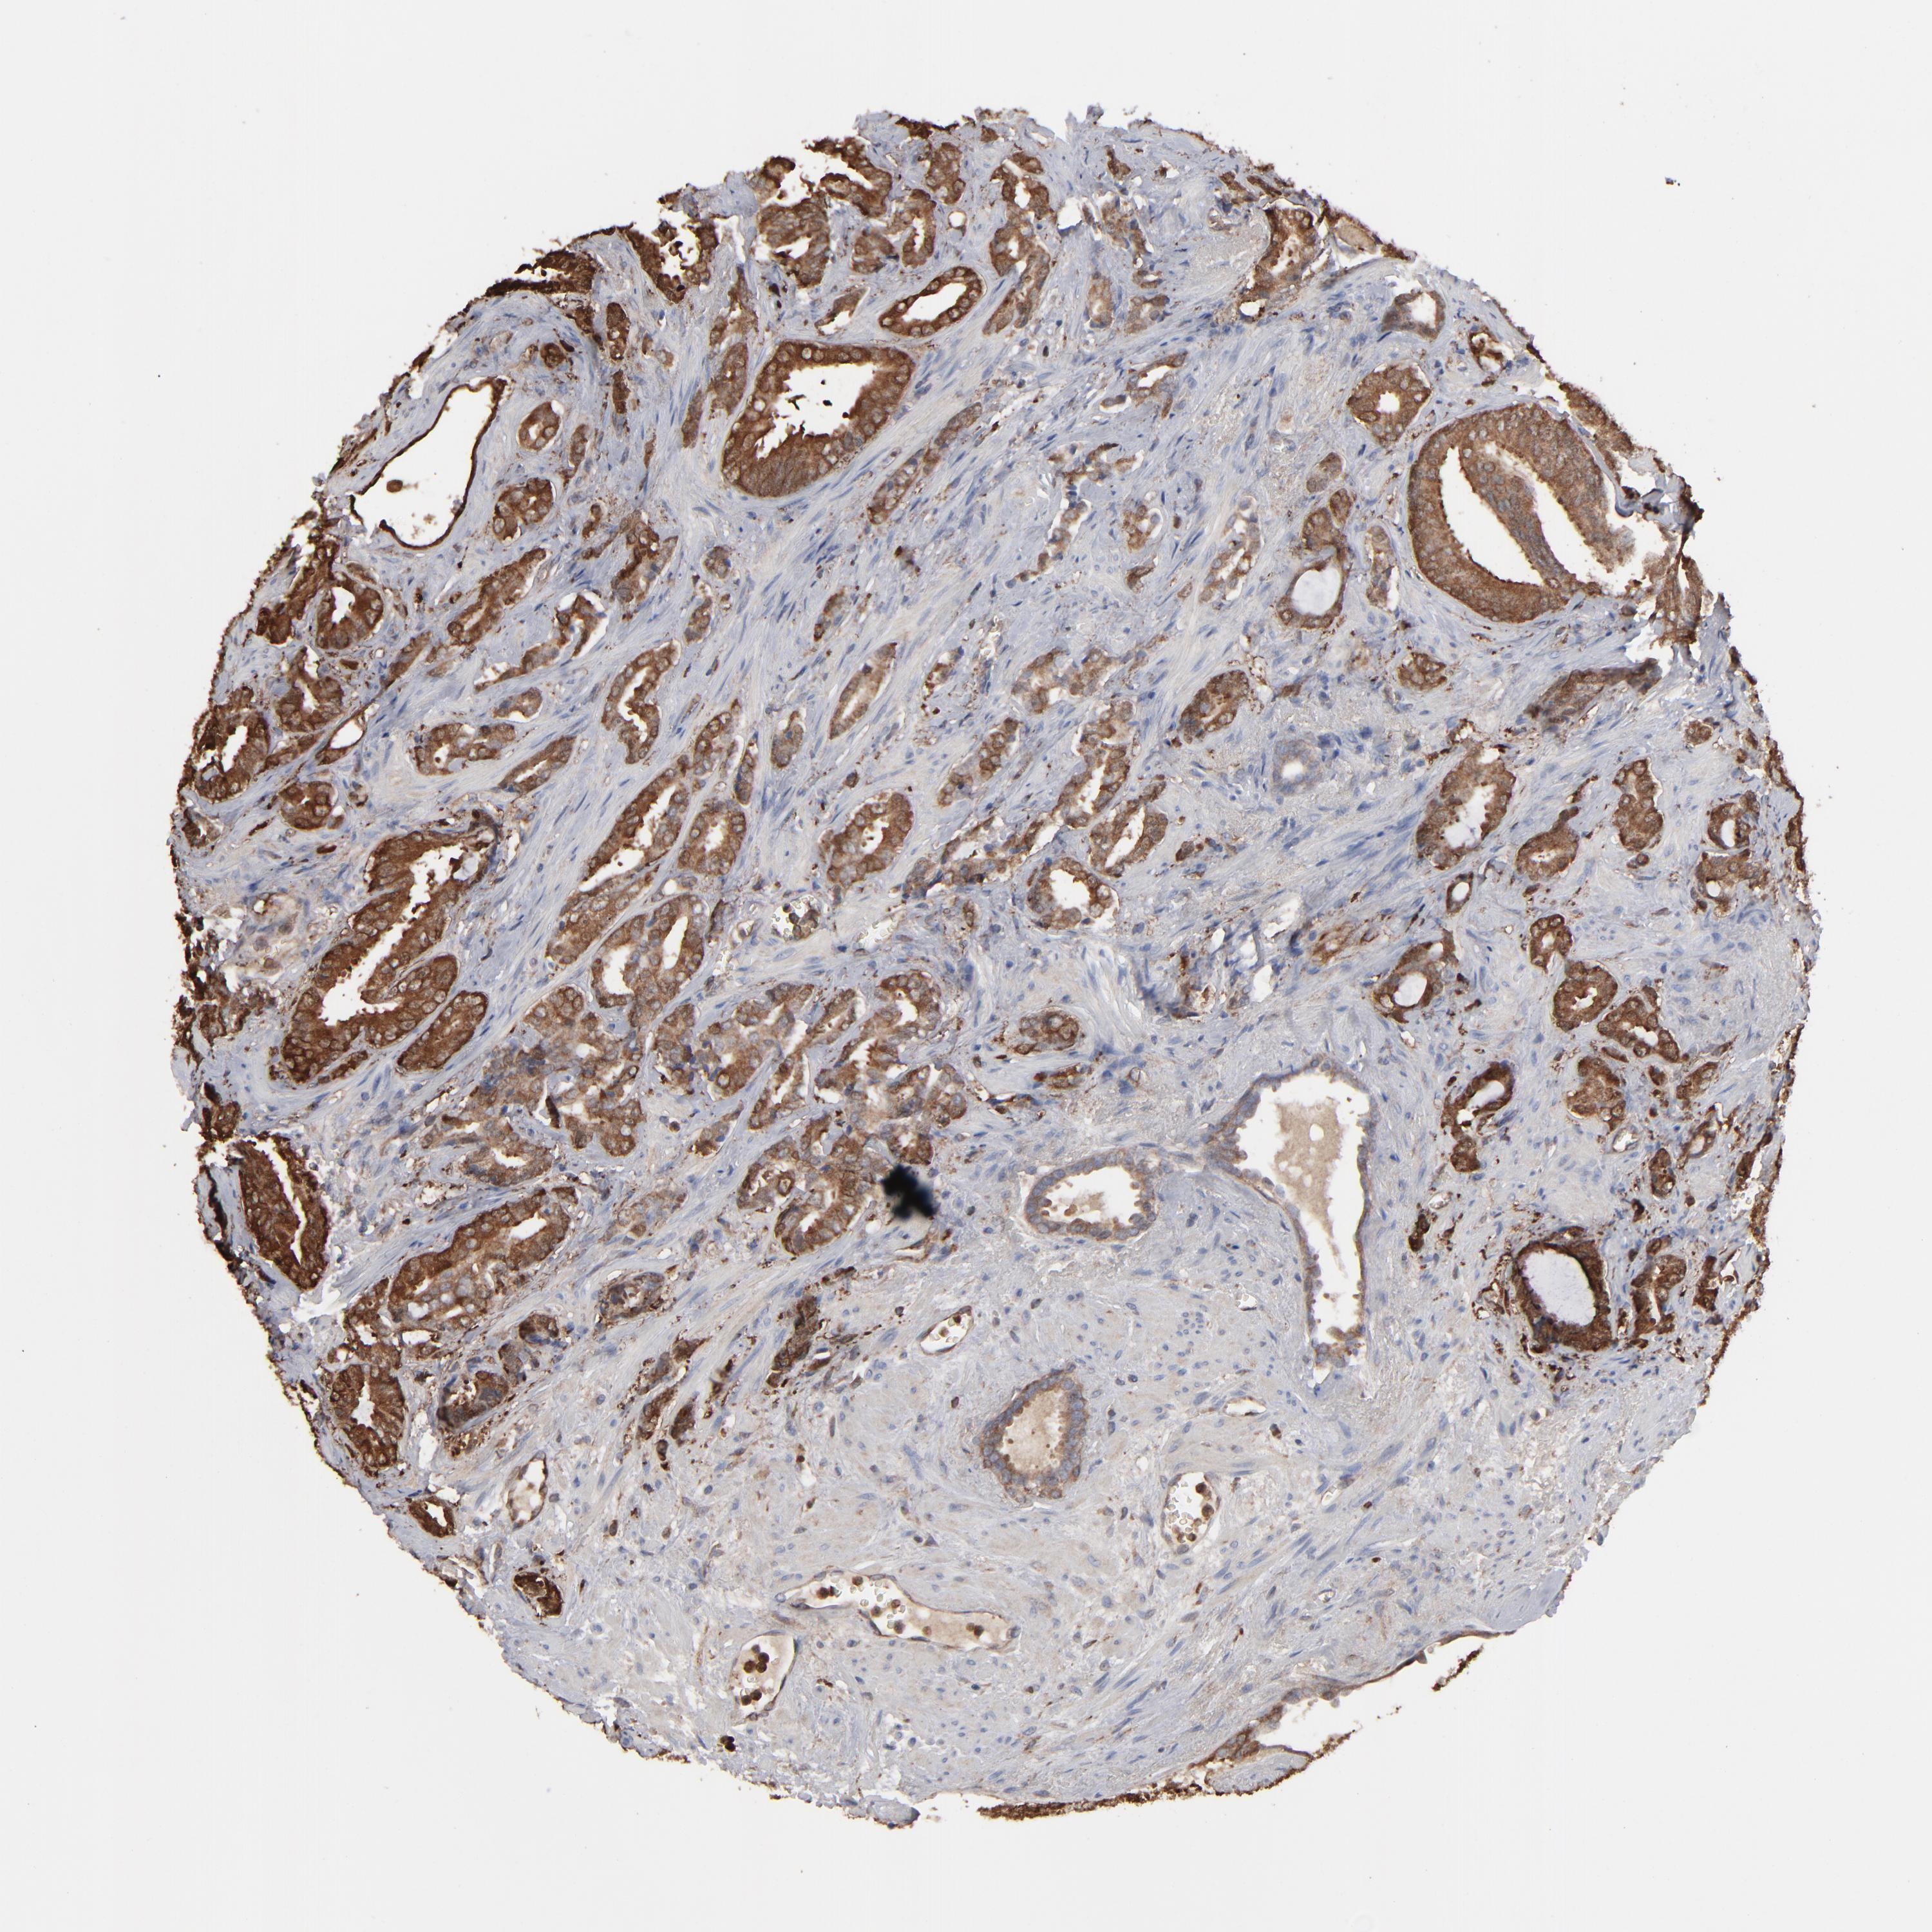

PROSTATE CANCER - Protein expressioni

A mouse-over function shows sample information and annotation data. Click on an image to view it in a full screen mode. Samples can be filtered based on level of antibody staining by selecting one or several of the following categories: high, medium, low and not detected. The assay and annotation is described here.

Antibody stainingi

Antibody staining in the annotated cell types in the current human tissue is reported as not detected, low, medium, or high, based on conventional immunohistochemistry profiling in selected tissues. This score is based on the combination of the staining intensity and fraction of stained cells.

Each image is clickable and will lead to virtual microscopy that enables deeper exploration of all samples and also displays staining intensity scores, fraction scores and subcellular localization as well as patient and tissue information for each sample.

Antibody HPA008467

Antibody HPA041113

Antibody CAB002169

Antibody CAB076057

Staining

High

Medium

Low

Not detected

Intensity

Strong

Moderate

Weak

Negative

Quantity

>75%

75%-25%

<25%

None

Location

Nuclear

Cytoplasmic/membranous

Cytoplasmic/membranous,nuclear

Adenocarcinoma, Low grade

Adenocarcinoma, High grade

Adenocarcinoma, NOS

Adenocarcinoma, Medium grade